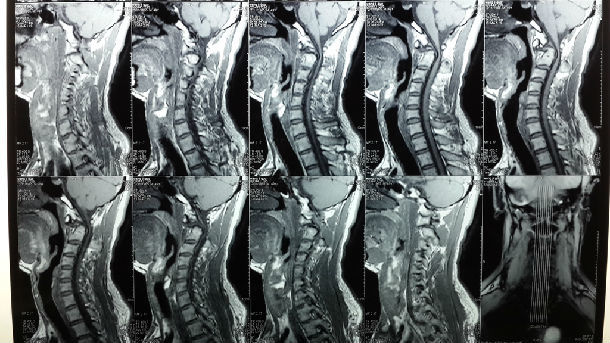

术前磁共振MRI示寰枢椎脱位,颈延脊髓明显受压